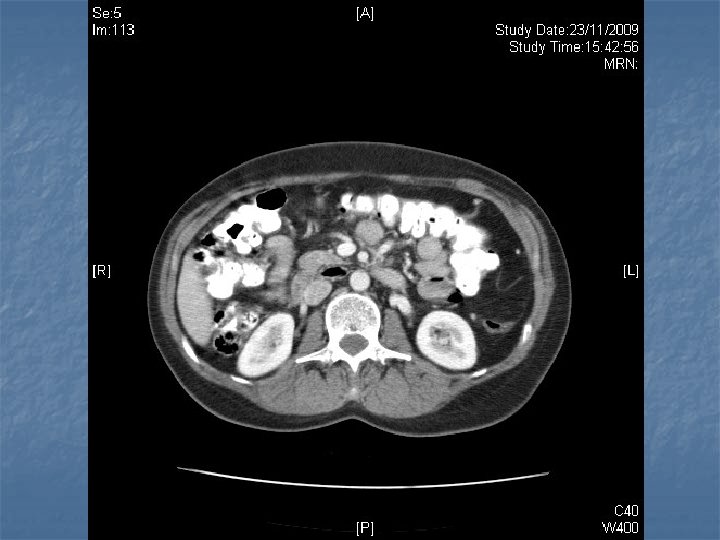

n n n PRETREATMENT INVESTIGATIONS: FBC, Renal and liver function, LDH, urate, Ig. GS. Histology review. Marrow aspirate+trephine (cytogenetics, immunology) CD 4 , HIV viral load. CT Scans. (MR Brain) (PET scan ) Echo / LVEF CMV, Hep B+C, Toxoplasma serology MAI screen. LP for CSF cytology +/- intrathecal Rx. (DLBC , Burkitt, Plasmablastic).